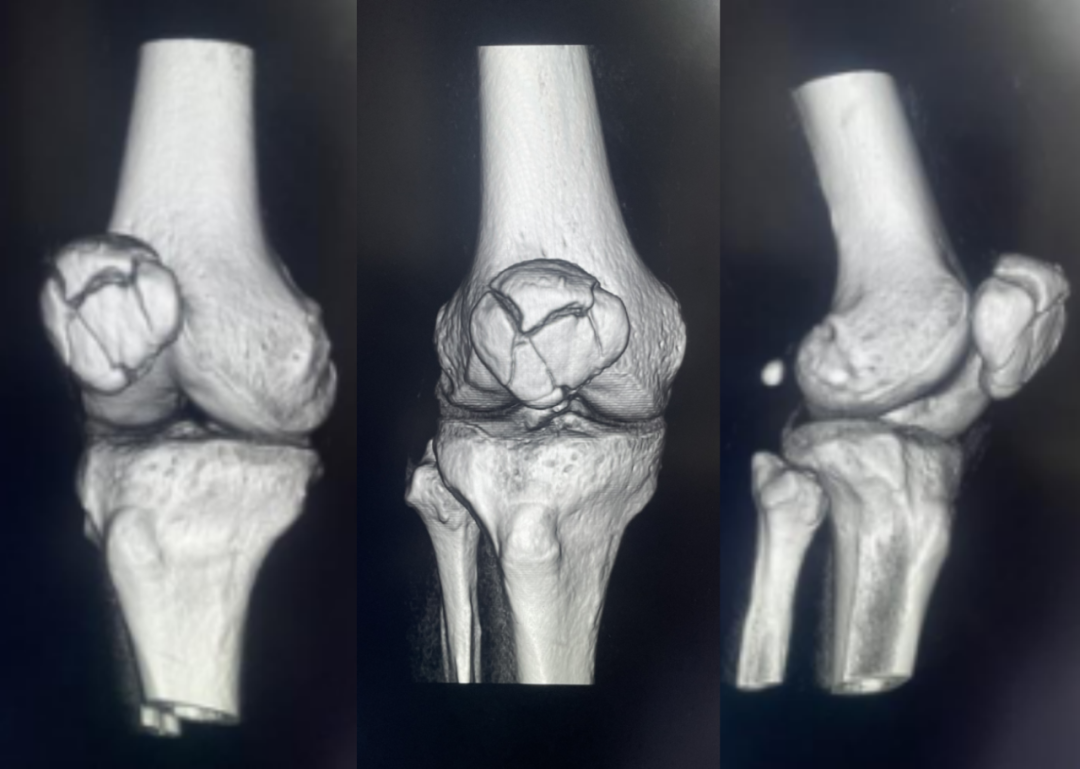

髌骨骨折只占全身骨折的 1%,治疗方式的选择和并发症的防治尤其要注意,急诊来了髌骨骨折患者,你怎么处理?髌骨是人体最大的籽骨,位于膝关节伸膝装置内。解剖特点包括近端宽大的基底和关节外的远侧尖端,前面位于关节外,后面为关节面。股直肌和股中间肌止于髌骨基底部,股内侧肌和股外侧肌止于髌骨的两侧。髌腱起于髌骨尖端,止于胫骨结节。髌骨骨折约占所有骨折的 1%,主要由直接暴力造成,如跌倒时跪地或膝关节屈曲时受到打击。典型的体征包括关节肿胀、压痛、伸膝功能部分或完全丧失。除以主诉和典型体征外,膝关节 X 线片也是必不可少的一项辅助检查,以膝关节正侧位 X 线片最常见,如果怀疑纵向骨折,膝关节屈曲 45° 时髌骨 30° 切位片可以辅助诊断。对于骨折不愈合、畸形愈合所致的关节面不平整以及髌股关节对应关系不良可采用 CT 检查。MRI 有助于诊断软骨缺损和损伤。34-B 型(部分关节内骨折,伸膝装置完整,如纵行骨折)髌骨下极骨折袢钢板结合克氏针、张力带固定 图源:作者提供

拉力螺钉加张力带钢丝固定或经胫骨结节绕髌环扎;经骨缝合撕裂的肌腱加髌骨和胫骨结节间钢丝环绕以加固缝合;袢钢板固定。无移位采用非手术治疗;移位并且单纯骨折采用横向拉力螺钉固定,骨质疏松患者需加环扎固定;对于多骨折块(星状)则采用髌骨环扎加张力带进行固定。克氏针加张力带钢丝;有第三个骨折块则采用拉力螺钉或克氏针加张力带钢丝固定;对于 4 个或 4 个以上的骨折块采用克氏针加螺钉加张力带钢丝进行固定;对于严重粉碎和软骨面广泛破坏的髌骨骨折,髌骨部分或完全切除也是一种可行的办法。